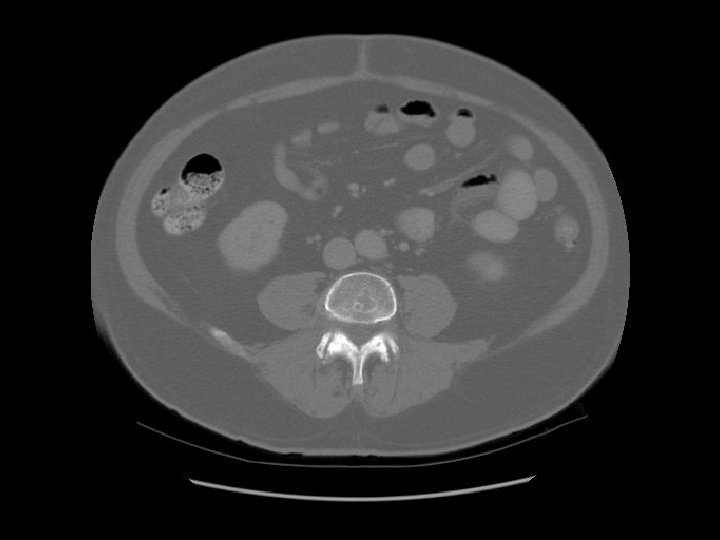

Transverse colon Ileum

Kidney Right Kidney

Descending colon Right

Renal pelvis

Ascending colon Right colon with fecal material.